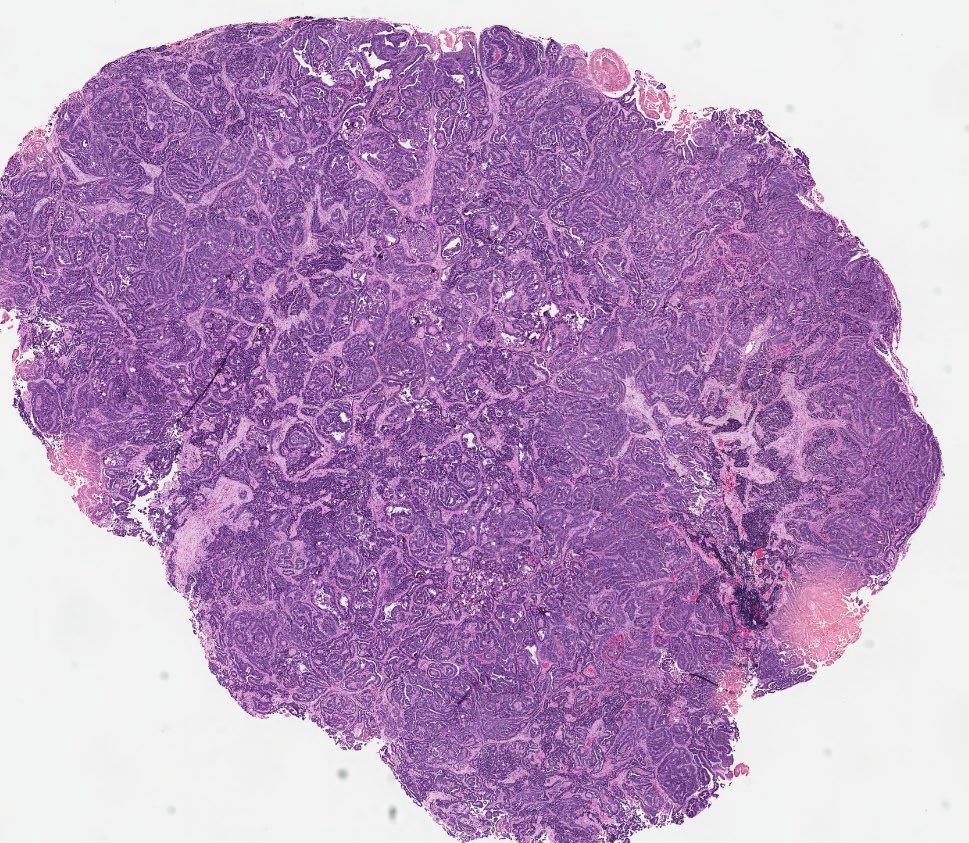

30 F. Mass in lumen of femoral vein. Diagnosis?

WSI digital slides: kikoxp.com/posts/21727

Immunostains: kikoxp.com/posts/21729